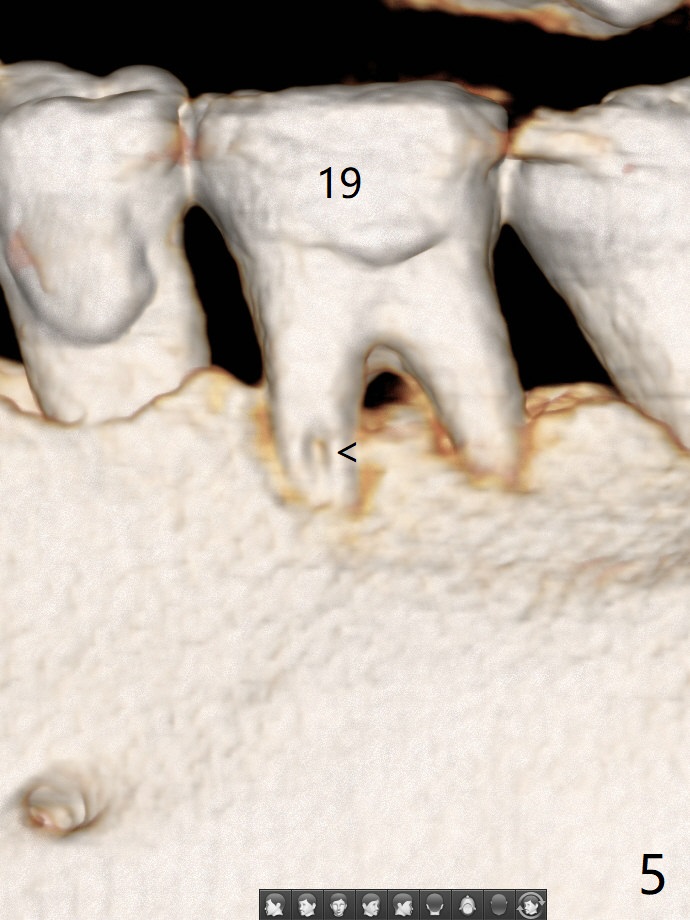

57岁女全口牙龈萎缩骨质吸收,其实卫生好,3号牙金属圈多年,治疗牙齿隐裂,骨质吸收和牙裂与咀嚼力大有关。最近抱怨19,30号牙敏感(图一),涂脱敏剂无效,拍摄根尖片(图二,三),显示30号牙远中根,19号牙近中根从牙槽嵴开始仿佛纵裂(图二,三),牙周探针患根周围触痛。磨牙牙根好像一段式植体,断裂总是发生于牙槽嵴顶,不过是横裂,所以一定要植入牙槽嵴之下,还要考虑今后牙槽嵴吸收。如何确诊牙根纵裂呢?例如19号牙CT显示颊侧近中根(图四,六:B)牙槽嵴处断裂(箭头)。利用一个叫Profile Program(Profilogram)测定近中根横断面平均密度,舌侧密度基本均匀(图七),而颊侧断裂处密度突然降低(图八)。当断裂还不是很明显时(隐裂),测定平均密度就显得重要,帮助诊断。